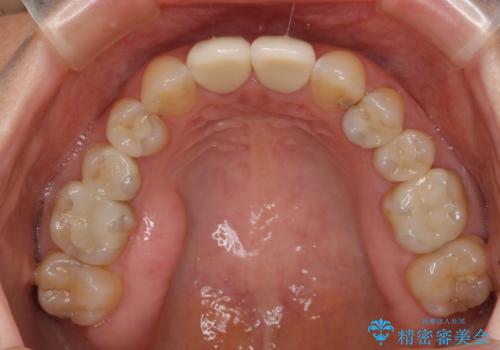

- 上顎2前歯の色を気にして来院された患者様です。

2本ともに虫歯治療による充填材の変色などによりつぎはぎのような前歯となっていたため、オールセラミッククラウンにて補綴治療を行うこととしました。

今後ホワイトニングをする予定とのことで、少し明るめのトーンに仕上げました。